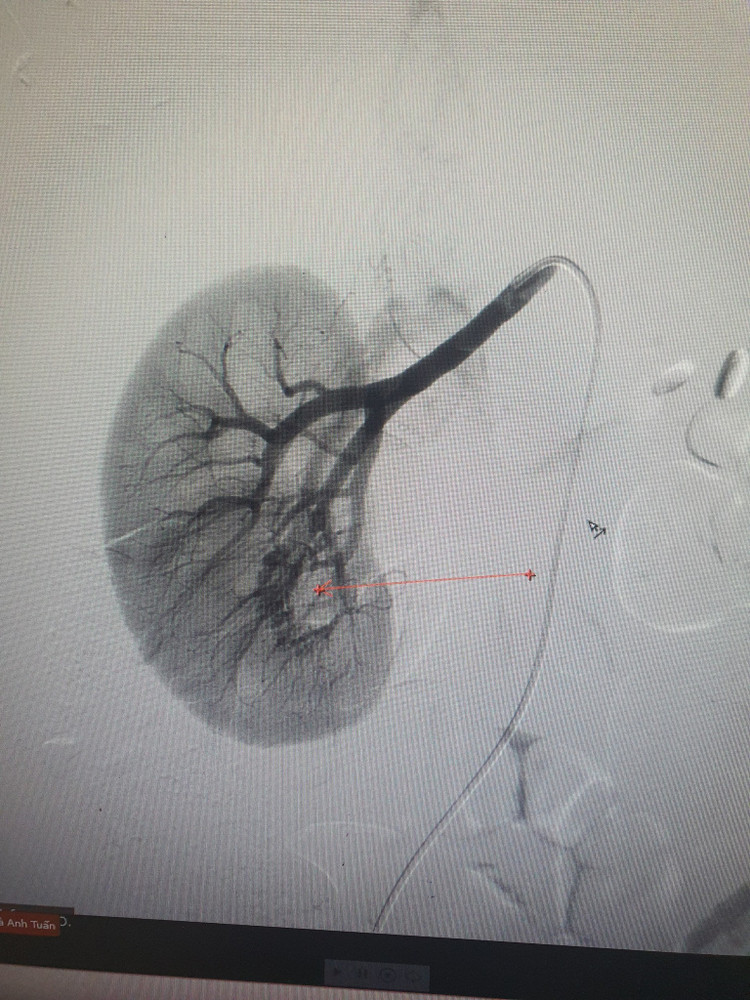

Qua siêu âm các bác sĩ chẩn đoán: bệnh nhân bị giãn thận - niệu quản phải do cục máu đông niệu quản 1/3 trên. Bệnh nhân được chỉ định chụp cắt lớp vi tính ổ bụng có tiêm thuốc cản quang đánh giá thêm. Kết quả cho thấy hình ảnh: thận phải đài bể thận giãn độ II, niệu quản giãn/ máu cục niệu quản 1/3 trên. Theo dõi ổ dị dạng thông động - tĩnh mạch (AVM) cực dưới bể thận phải, kích thước nidus khoảng 27x11mm, dẫn lưu về tĩnh mạch thận.

Các bác sĩ chẩn đoán bệnh nhân bị dị dạng thông động tĩnh mạch (AVM) thận phải. Hội chẩn liên khoa và các chuyên gia Bệnh viện Bạch Mai đánh giá AVM thận phải dọa vỡ nguy hiểm, các bác sĩ quyết định can thiệp nút mạch điều trị khối dị dạng thông động tĩnh mạch thận để tránh biến chứng vỡ mạch khó lường, nguy cơ chảy máu, đe dọa tính mạng người bệnh.

Ca can thiệp được thực hiện tại trung tâm Tim mạch - điện quang can thiệp Bệnh viện Đa khoa Hùng Vương diễn ra thuận lợi, bệnh nhân tỉnh táo trong suốt quá trình can thiệp, không đau đớn. Các bác sĩ đã thực hiện can thiệp nút tắc ổ dị dạng thông động - tĩnh mạch bằng keo sinh học.

| Dị dạng động tĩnh mạch (AVM) thận trên phim chụp |

Dị dạng động tĩnh mạch (AVM) thận là sự lưu thông bất thường giữa động mạch và tĩnh mạch mà không qua đường mao mạch. Đây là tổn thương hiếm gặp chiếm 0,04% dân số, giai đoạn đầu khó phát hiện qua siêu âm nên bệnh thường chẩn đoán muộn, nhờ sự phát triển của các phương pháp chẩn đoán hình ảnh hiện đại nên có thể phát hiện sớm dị dạng này.